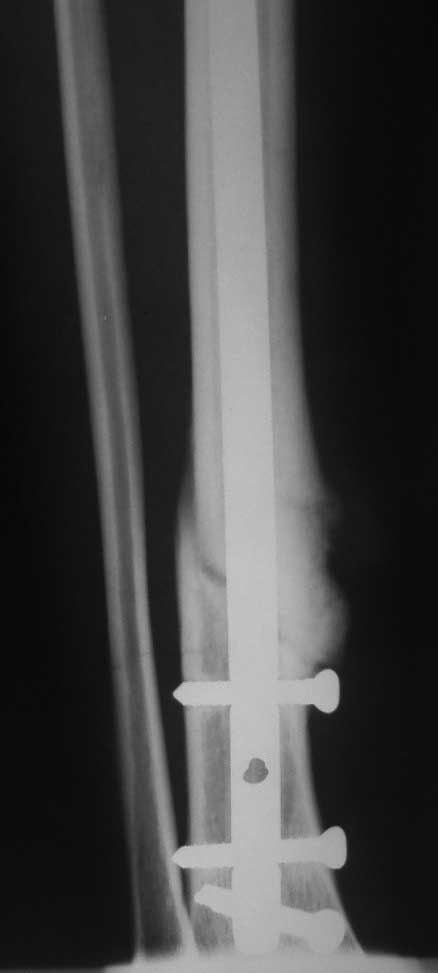

[Ortho] Несращение перелома н\3 б\берцовой кости (ложный сустав)

Пациентка проперирована в марте 2011 года. На Р-граммах несращение. Пробывали давать

нагрузку - появлялись боли в области перелома, опять разгрузка...

Сейчас поступила в стационар. Думаем что делать. Можно конечно убрать стержень и сделать повторный

синтез пластиной с пластикой по Хохутову. Интересна альтернатива!? Все винты в стержне -

статические (проксимально - 2, дистально - 3)